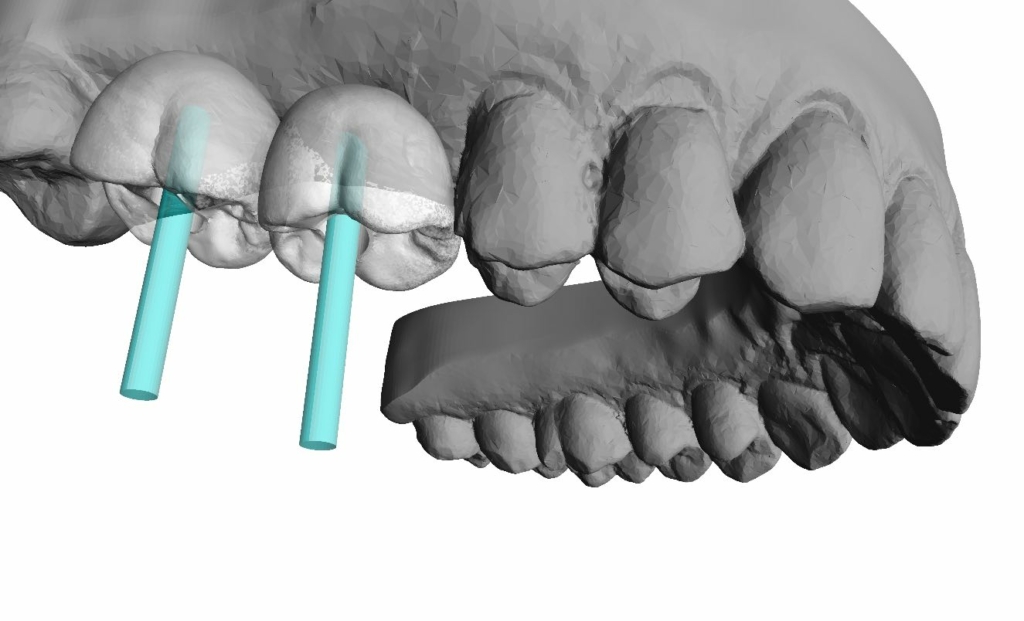

Rehabilitación completa maxilar (Full Arch)

Paciente: mujer, 59 años, edentulismo parcial.

Tratamiento: colocación de 6 implantes inmediatos con férulas apilables y prótesis provisional instantánea parcial.

Tiempo de intervención: 2 horas y 30 minutos.

Beneficios: intervención rápida y precisa, manejo conservador del tejido blando, estética y funcionalidad instantánea, alta satisfacción del paciente.

Estos casos ilustran cómo nuestro flujo BRDP y la cocreación clínica permiten resultados predecibles y eficientes, optimizando tanto el tiempo de sillón como la experiencia de paciente y clínica.